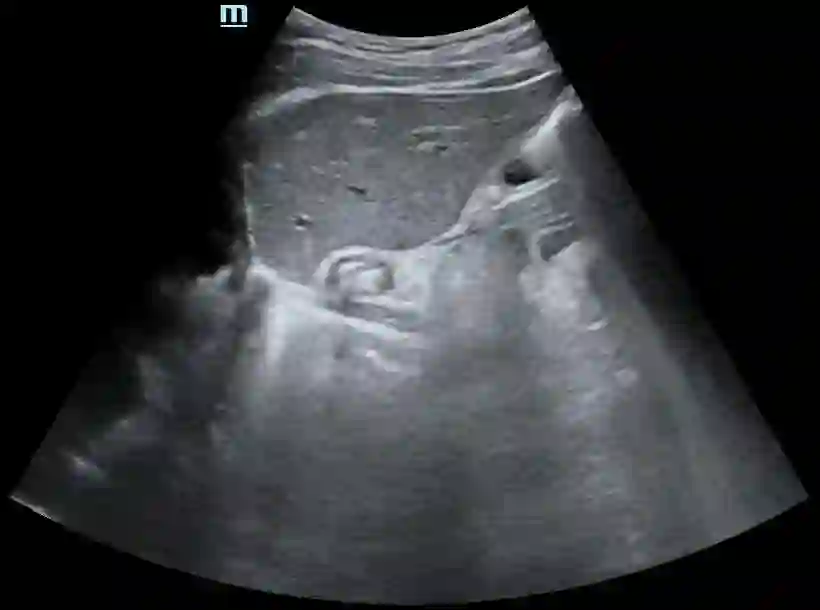

Most deep neural networks (DNNs) based ultrasound (US) medical image analysis models use pretrained backbones (e.g., ImageNet) for better model generalization. However, the domain gap between natural and medical images causes an inevitable performance bottleneck. To alleviate this problem, an US dataset named US-4 is constructed for direct pretraining on the same domain. It contains over 23,000 images from four US video sub-datasets. To learn robust features from US-4, we propose an US semi-supervised contrastive learning method, named USCL, for pretraining. In order to avoid high similarities between negative pairs as well as mine abundant visual features from limited US videos, USCL adopts a sample pair generation method to enrich the feature involved in a single step of contrastive optimization. Extensive experiments on several downstream tasks show the superiority of USCL pretraining against ImageNet pretraining and other state-of-the-art (SOTA) pretraining approaches. In particular, USCL pretrained backbone achieves fine-tuning accuracy of over 94% on POCUS dataset, which is 10% higher than 84% of the ImageNet pretrained model. The source codes of this work are available at https://github.com/983632847/USCL.